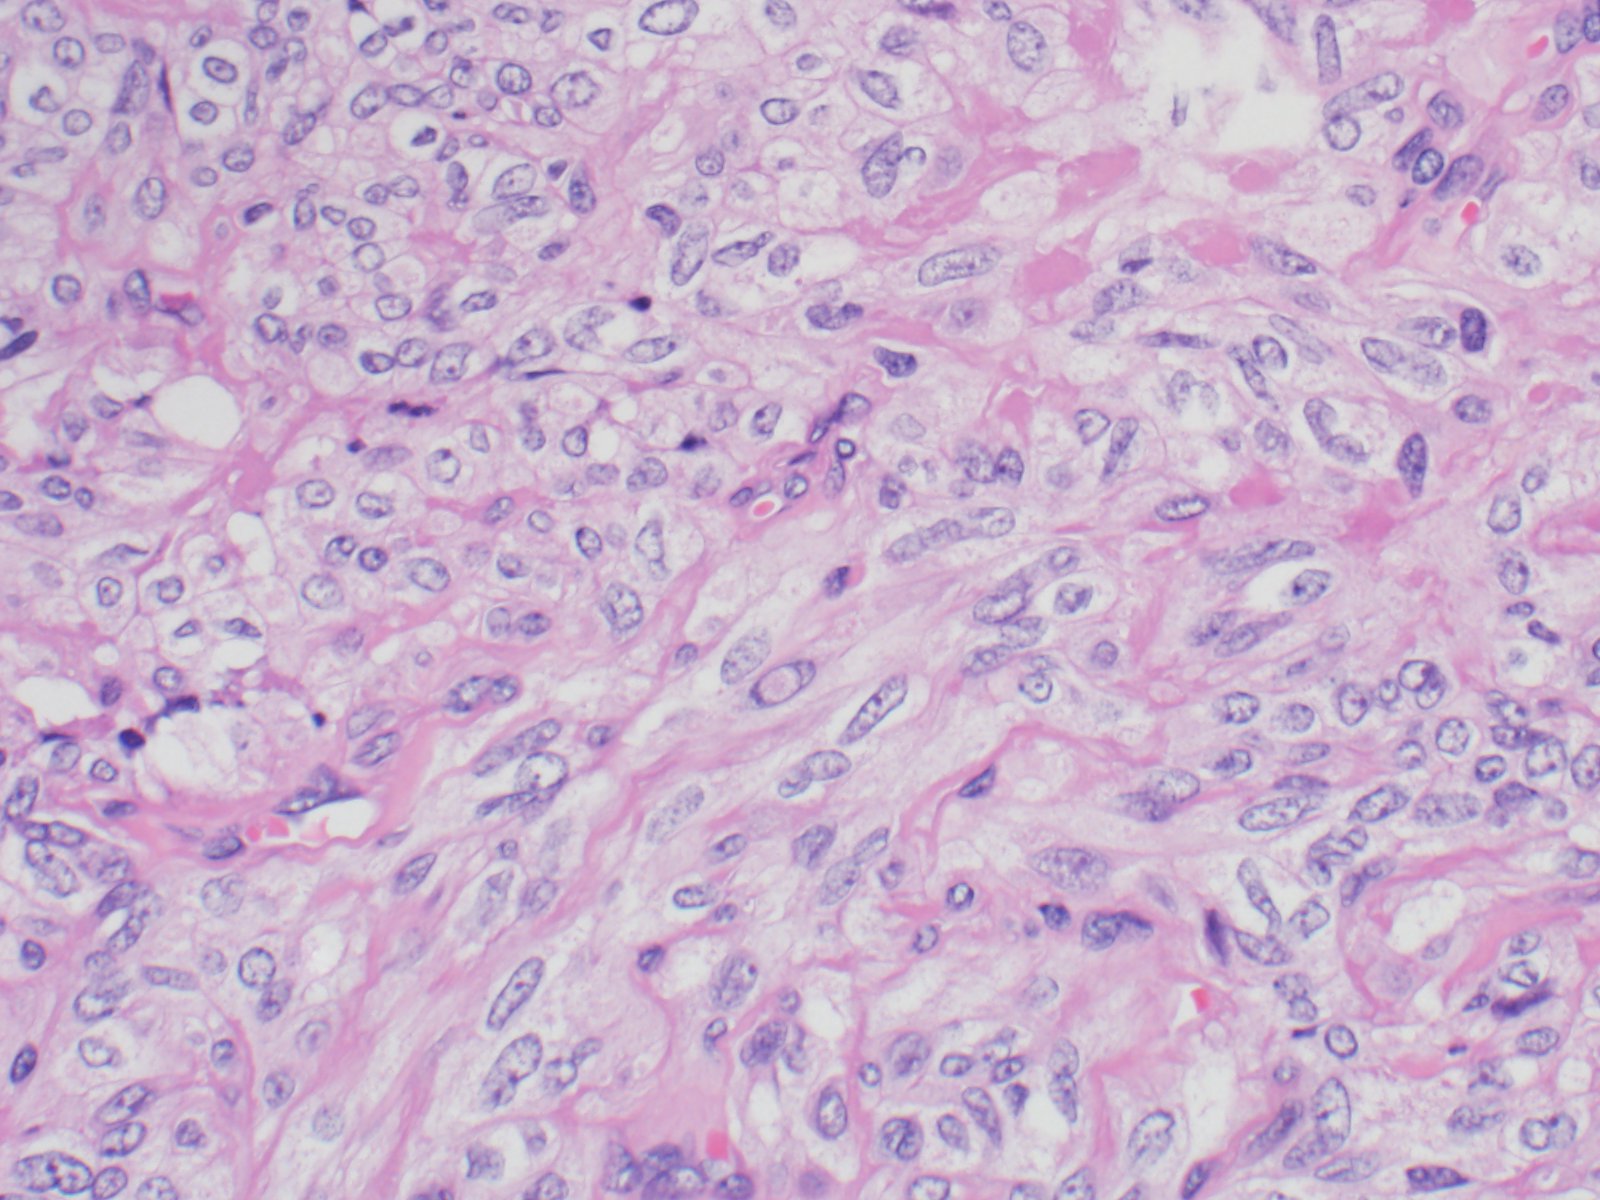

The specimen consists of variably sized fragments of cells with elongated/spindled nuclei, intranuclear inclusions, moderate amounts of cytoplasm, and some eosinophilic amorphous material.

HTT of the thyroid is a rare follicular derived neoplasm that occurs more commonly in middle-aged euthyroid females, incidentally found. They have a characteristic rearrangement of GLIS and have a favorable prognosis. Cytologically, the cells resemble papillary thyroid carcinoma, medullary thyroid carcinoma and non-invasive follicular thyroid neoplasm with papillary-like nuclear features. On surgical pathology, HTT exhibits a prominent trabecular pattern, abundant intratrabecular hyalinized stroma and characteristic nuclear features of papillary carcinoma.